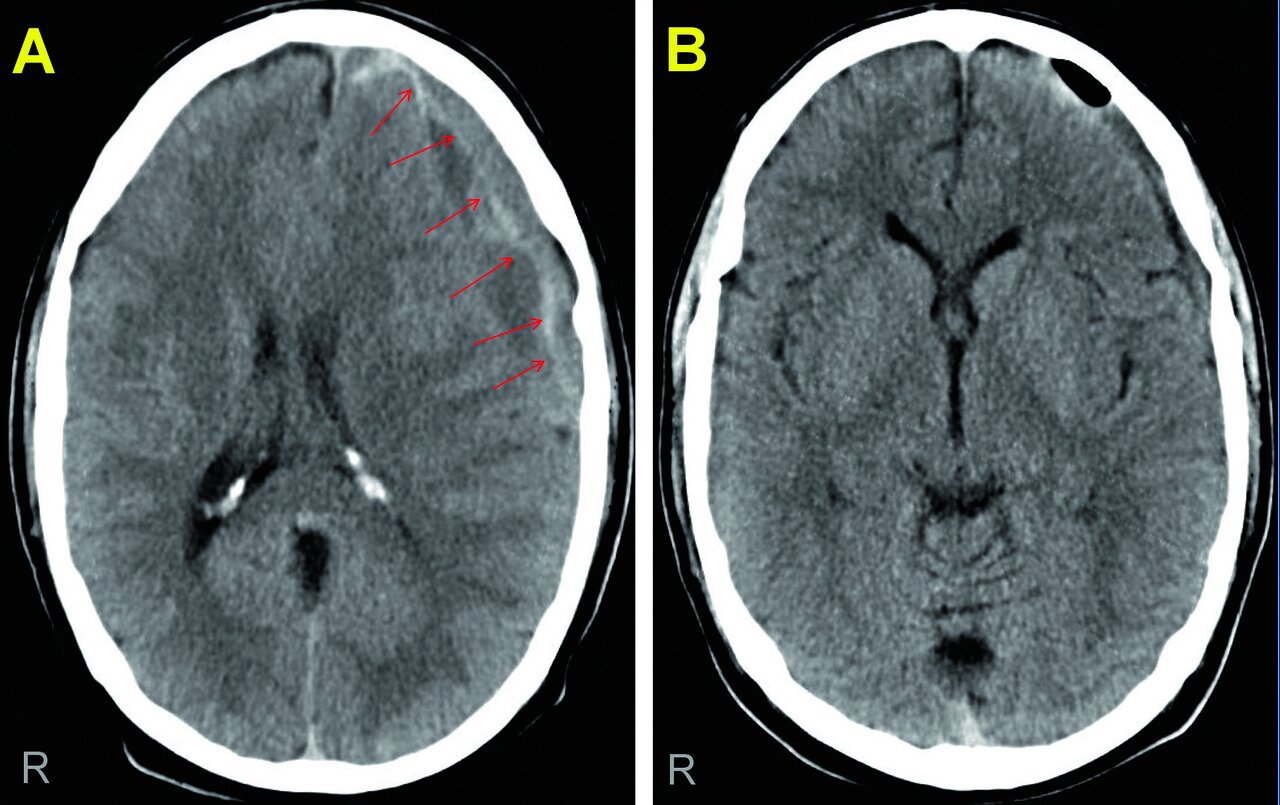

Die kraniale Computertomografie zeigte ein chronisches Subduralhämatom links frontotemporal (s. Abb. 1). In der präoperativen Gerinnungsdiagnostik fand sich passend zur Medikamentenanamnese eine aufgehobene Thrombozytenfunktion. Durch eine Bohrlochtrepanation gelang es, das Hämatom vollständig zu entleeren. Nach wenigen Tagen war der Patient wieder beschwerdefrei.

Abb.1: Chronisches Subduralhämatom (Pfeile) mit Verdrängung der Mittellinie nach rechts (A). Die Bohrlochtrepanation  führte zu einer vollständigen Entleerung, die Falx cerebri ist wieder mittelständig (B). Abb.1: Chronisches Subduralhämatom (Pfeile) mit Verdrängung der Mittellinie nach rechts (A). Die Bohrlochtrepanation führte zu einer vollständigen Entleerung, die Falx cerebri ist wieder mittelständig (B). © Schulz C et al. Wehrmedizinische Monatsschrift 2022; 66: 214-223; DOI: 10.48701/opus4-21 © Beta Verlag & Marketinggesellschaft mbH, Bonn